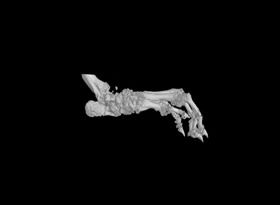

1.掃描重構:常規(guī)樣本,一個視野可以掃的樣本,按以上報價。對于一些特殊樣本或較大樣本,可能需要多個視野掃,費用按相應的視野數(shù)計算,比如大鼠爪子至少需要3個視野。